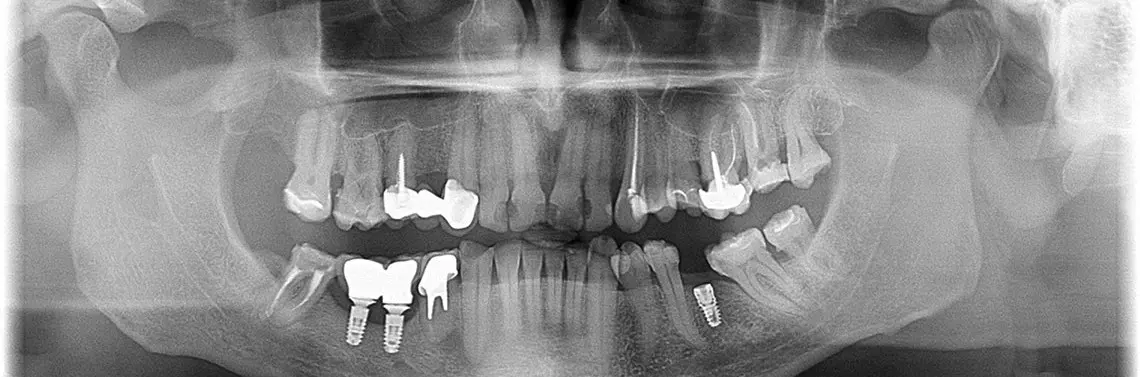

Czy uszkodzenia w obrębie implantu u pacjenta z licznymi obciążeniami ogólnoustrojowymi zawsze muszą się kończyć eksplantacją?

Implantoprotetyka i chirurgia implantacyjna stale się rozwijają, wprowadzane są nowe metody i materiały. Mimo to zdarzają się sytuacje, gdy implant lub jego elementy zostają uszkodzone. Nieraz przyczyniają się do tego sami pacjenci, którzy nie zawsze stosują się do zaleceń dotyczących higieny jamy ustnej lub zaplanowanego leczenia. W przypadku uszkodzenia uzupełnienia implantoprotetycznego może dojść do konieczości jego eksplantacji. Czasami jednak udaje się tego uniknąć.

Implantoprotetyka i chirurgia implantacyjna od lat posługują się ściśle określonymi zasadami, które w miarę postępu badań, doświadczenia, wprowadzania nowych technologii i materiałów co jakiś czas ulegają stosownym modyfikacjom. Mimo tych zasad zdarzają się przypadki pękania lub odłamywania się samych elementów nadbudów protetycznych. Awarie te dotyczą również elementów łącznikowych przykręcanych do ciała implantu/implantów i samych wszczepów. Przyczyn ewentualnych niepowodzeń technicznych może być wiele – od złego rozplanowania pogrążania implantów, ich niewłaściwej średnicy, długości, poprzez błędy w projektowaniu i samym wykonawstwie części protetycznej, po ukryte wady materiałowe czy przeciążenia konstrukcyjne oraz wady odlewnicze dotyczące wszystkich trzech składowych: ciała implantu, elementów łącznikowych i samej nadbudowy protetycznej. Struktury te nie są w stanie znieść generowanych przez pacjenta sił okluzyjnych, jego patologicznych nawyków zgryzowych czy podawanych w wywiadzie uszkodzeń jatrogennych, ponieważ niektórzy pacjenci często uważają same implanty i wdrożone leczenie za remedium na dotychczasowe leczenie stomatologiczne [1–4].